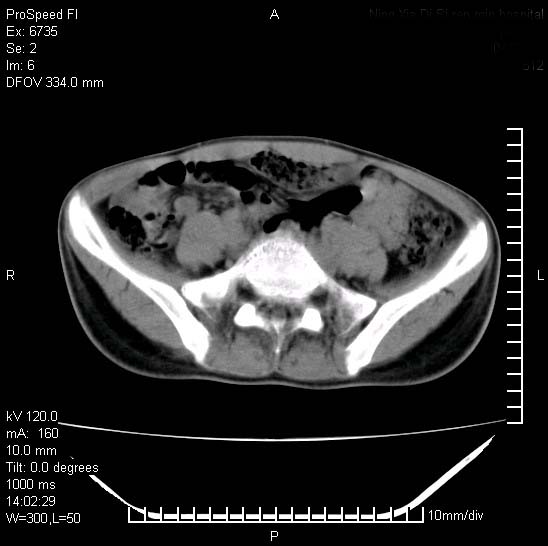

患者自诉胯部疼痛两年余,在当地服用中药,半月前至本院考虑骶髂关节结核,给予抗痨治疗。现发展至右下肢疼痛明显,活动受限,以膝关节处明显,拍膝关节平片无明显异常。

两侧骶骼关节改变,考虑强直性脊炎

左侧骶髂关节面限局性骨破坏,边缘硬化关节腔见钙化物;不出外tb

右侧骶髂关节也有类似改变,只是较左侧轻,首先考虑强直性脊柱炎,不除外结核,建议作hla-b27检查。

典型强脊炎改变,髋关节亦有累及

符合强直性脊柱炎表现。